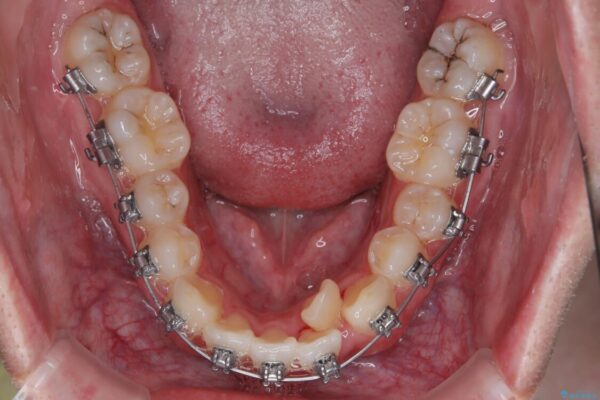

治療方針

このような歯列の狭さに起因するデコボコを改善するために、**MARPE(骨に固定する上顎急速拡大装置)**を使用して、上顎の横幅を拡大し、これにより歯が並ぶためのスペースを確保し、メタルブラケットを用いて歯列を整えていく計画としました。

治療途中

• 1年でここまで変わる!歯列のがたつきと正中のズレを改善した矯正治療(メタルブラケット×MARPE) 治療途中画像